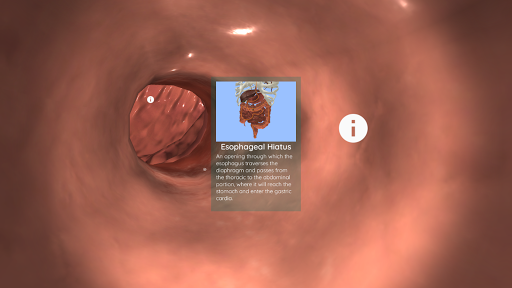

في وضع الواقع الافتراضي ، يجب إدراج الجهاز المحمول (الهاتف الذكي) في أداة الواقع الافتراضي للاستمتاع بتجربة غامرة بالكامل. يمكن للمستخدم التفاعل مع عناصر التحكم في التنقل وعناصر المعلومات التشريحية من خلال توجيهها.

على الرغم من أنه يوفر أفضل تجربة عند استخدامه في وضع الواقع الافتراضي ، إلا أنه يمكن للمستخدم الاستمتاع والتعلم مع تطبيق الهاتف المحمول هذا في وضع ملء الشاشة ، دون الحاجة إلى أداة الواقع الافتراضي.

يمكن أيضًا استخدام Anatomyou VR كأداة مفيدة للغاية لتعليم الطلاب في الفصل باستخدام إما الواقع الافتراضي (مع أدوات VR) أو وضع ملء الشاشة.

هذه نسخة تم تجديدها حديثا من Anatomyou VR. وتشمل الميزات: - تشريح الإنسان أكثر واقعية ، وتعزيز النماذج والقوام. - تفاعل أفضل للمستخدم في أوضاع الواقع الافتراضي والشاشة الكاملة. - القوائم والصور المجددة تماما يوفر الملاحة بديهية. - محتوى سريري إضافي التحقق من صحة من قبل خبرائنا. - يجب على المستخدمين السابقين قبول بعض الأذونات (GoogleVR SDK). لقد بذلنا الكثير من الجهد في هذه الترقية ، آمل أن تستمتع بها!